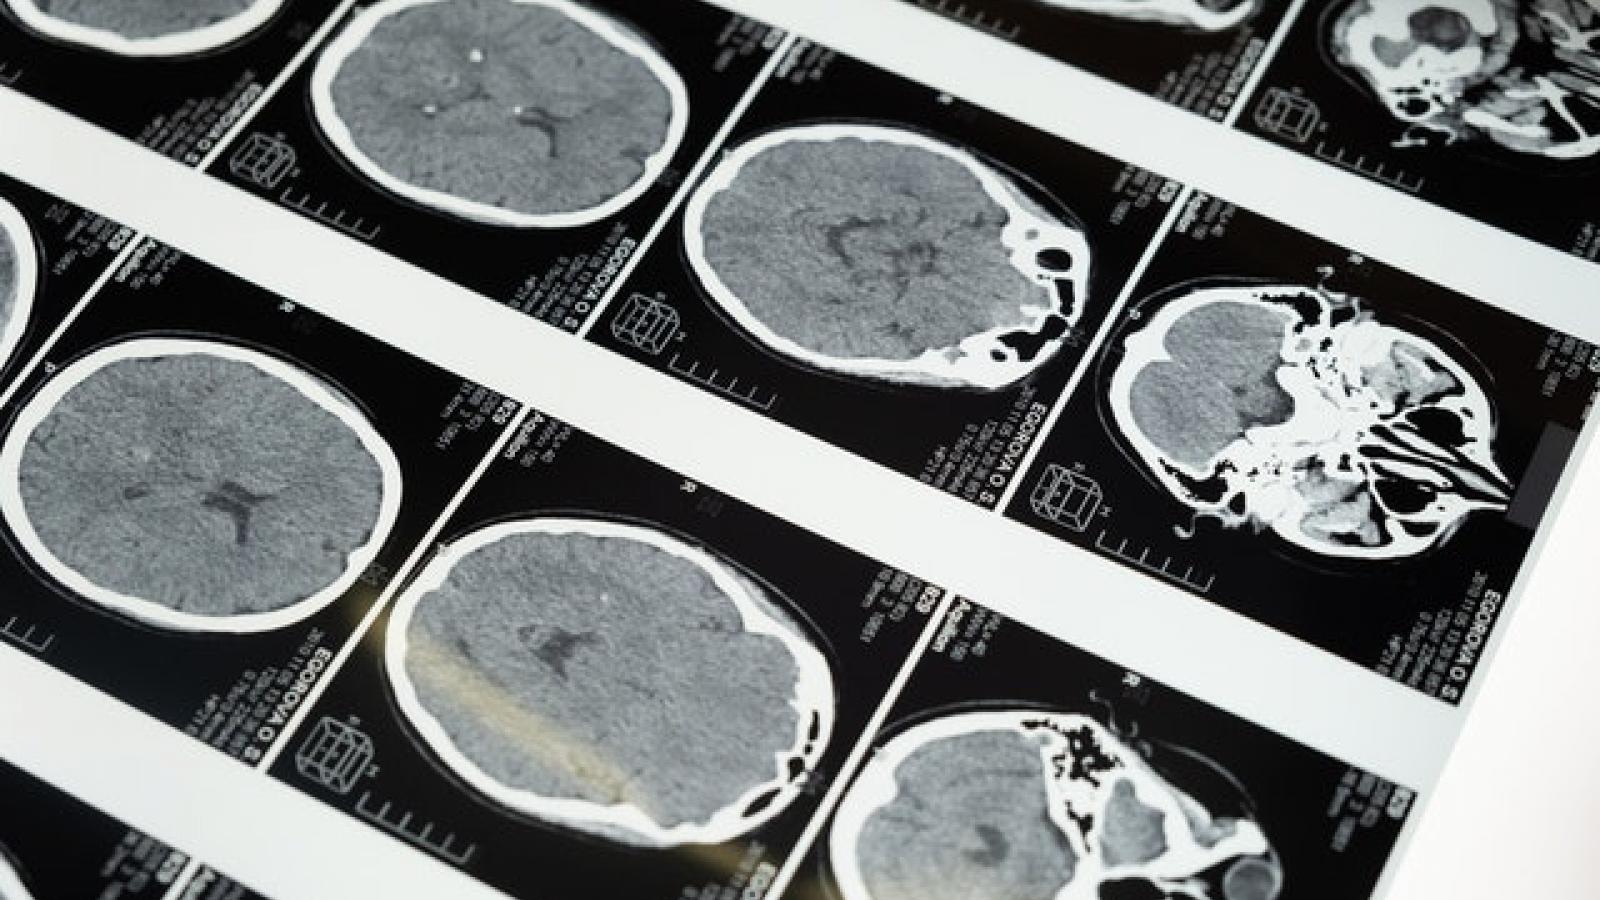

Brain scans mapped over different sections

A dynamic map of the whole brain during an epileptic seizure has been demonstrated by a team from the University of Melbourne in Australia and the University of Birmingham. That magnetoencephalographic (MEG) imaging can be used to help surgeons plan epilepsy procedures. Their results are published in Nature Communications.

In a proof-of-concept study, the researchers worked with 12 people with epilepsy to reveal the sources of their seizures using MEG imaging. From these data a computer model of the brain was constructed, which enable virtual surgeries to be performed. The computer model provides a 'real time' picture of brain areas involved in generating seizures. The researchers call their method virtual intracranial EEG (ViEEG).